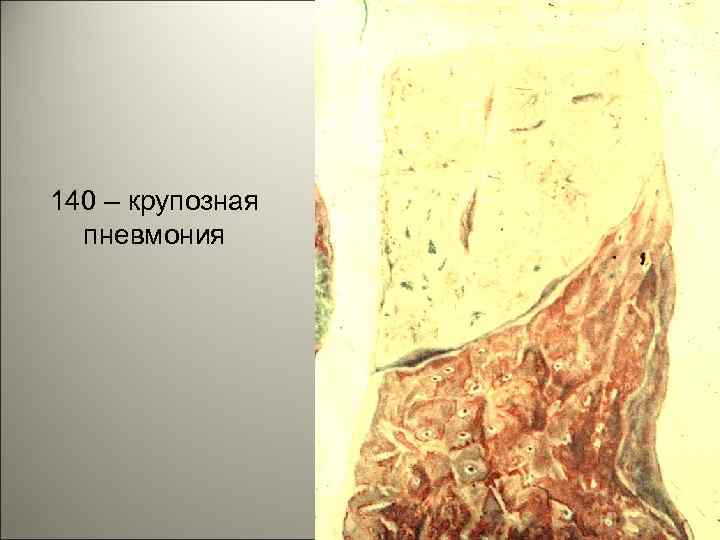

• Крупозная пневмония – острое инфекционно-аллергическое заболевание, при котором поражается одна или несколько долей легкого, в альвеолах появляется фибринозный экссудат, а на плевре – фибринозные наложения. 43

140 – крупозная пневмония 44